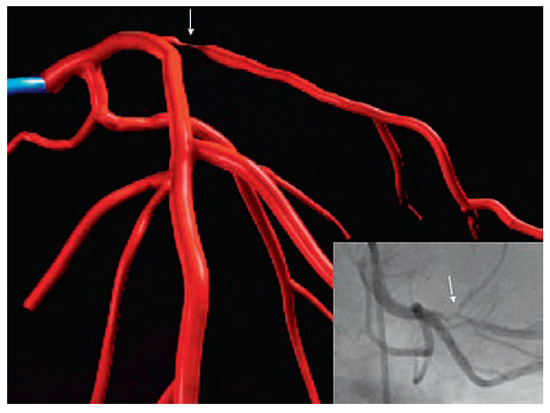

Coronary CT angiography (CTA) is emerging as a highly effective alternative imaging technique for the assessment of coronary artery disease (CAD). The rapid evolution of multidetector CT scanners has lead to major improvement in temporal resolution o...